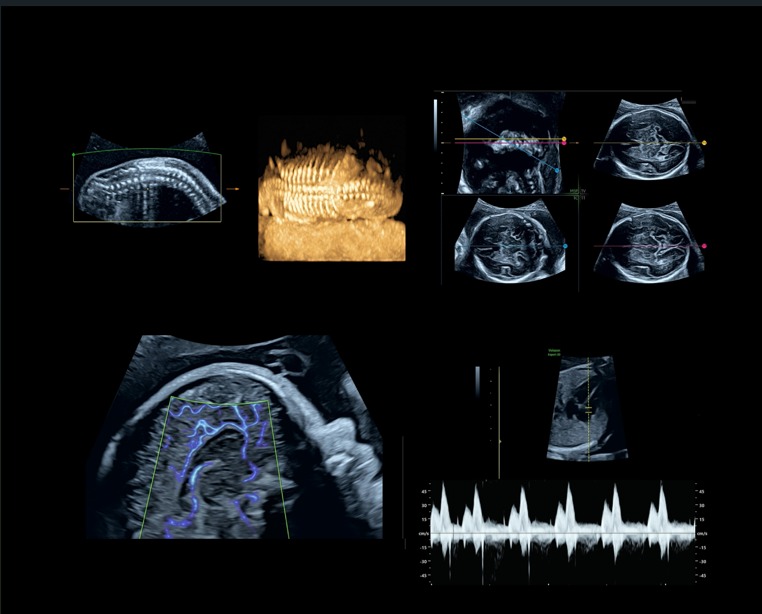

Deze exclusieve training wordt aangeboden in samenwerking met dr. Pascale G. Robles de Medina van Amsterdam UMC, expert op het gebied van o.a. de foetale circulatie en doppler onderzoek en een bijzonder talent om cursisten mee te nemen in de diepere lagen van ons vak. Zij zal tijdens deze training haar kennis en jarenlange ervaring met ons delen. Daarnaast is Gerjanne de With van GE Healthcare aanwezig als applicatiespecialist.